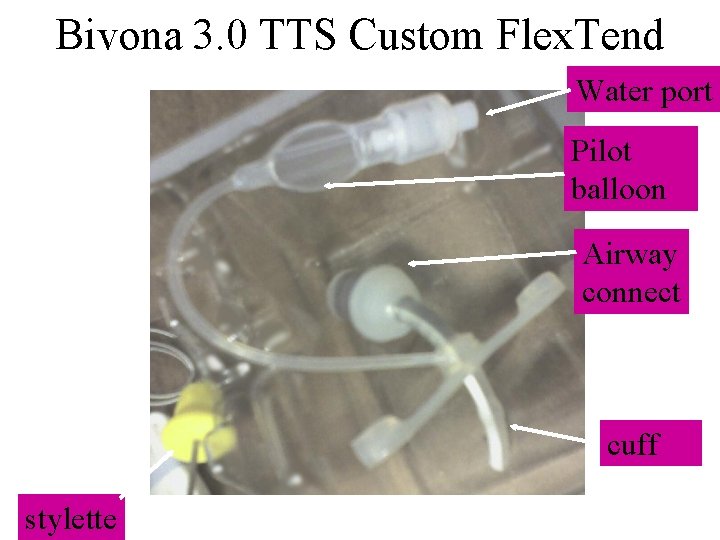

Bivona 3. 0 TTS Custom Flex. Tend Water port Pilot balloon Airway connect cuff stylette